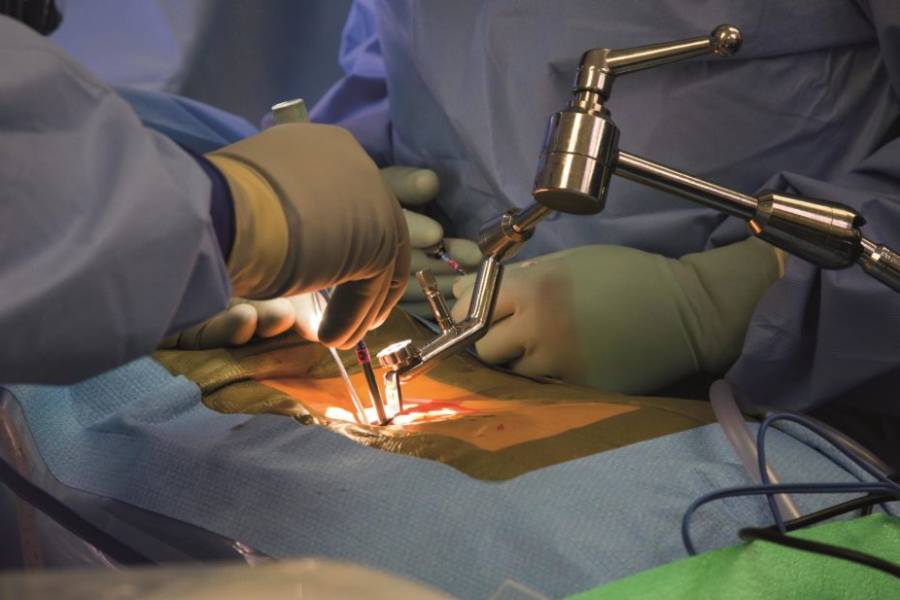

Dr. Prashant Kale is one of the best orthopedic doctors in Ahilya Nagar(Ahmednagar) and an additional director for Arogyasadan Multispeciality Hospital, Ahilya Nagar(Ahmednagar). They have nearly 15+ years of experience in Orthopedics treatment and Surgeries He is the “Gold Medalist” orthopedic Surgeon in DNB-Orthopedics. They have an expert in Knee Replacement Surgery, Revision surgeries, and a master of complex Joint Replacement Surgery. He has performed over 8000+ successful orthopedic surgeries to date. Well Versed and an established high volume surgeon dealing with Joint Replacement, Arthroscopy, Spine, Ilizarov, and complex trauma. Due to wide experience in orthopedic surgeries makes him one of the best orthopedic surgeons in Ahilya Nagar(Ahmednagar).

He qualified from the prestigious Rural Medical College of Pravara Medical Trust, Maharashtra. He completed his Diploma in Orthopedics from Dr. VNP Medical College and Health Sciences, Nashik in 2012. He obtained his DNB in Orthopaedics from the Malabar Institute of Medical Sciences, Calicut, Kerala in 2015. He is also an accredited & best Joint Replacement Surgeon in Ahilya Nagar(Ahmednagar) and has completed Advance training in the Adult Joint Replacement and Revision Surgeries from AIIMS, New Delhi in 2018.

EXCELLENTTrustindex verifies that the original source of the review is Google. Dr. Prashant Kale recently performed surgery on my left shoulder at Arogyasadan Hospital. The doctors explained the entire process to me thoroughly before the operation. The surgery went very well. The post-operative treatment process was also excellent. The hospital staff is extremely helpful and supportive. Facilities of the highest quality, like those in Pune or Mumbai, are available here. My experience with Dr. Kale has been outstanding.Posted on GoogleTrustindex verifies that the original source of the review is Google. Time per hospital service and cearing pesentPosted on GoogleTrustindex verifies that the original source of the review is Google. One of the best Ortho surgen Doctor I have been visited,I mate with an accident with fractured leg. It was so critical that everyone was worried.My friend recommended me to visit Dr Prashant kale and had the best results ..I was able to walk within 16 days . I personally recommend you to visit ..Posted on GoogleTrustindex verifies that the original source of the review is Google. I have taken a consultation for my mother ...she got best results in few days...I was very anxious about my mother...I already took consultation for her in other hospitals but she didn't get any relief.Posted on GoogleTrustindex verifies that the original source of the review is Google. I visited Arogyasadan Hospital, Ahilya Nagar for orthopedic treatment under Dr. Prashant Kale. He is very experienced, listens patiently, and explains the treatment in simple words. The treatment was effective and satisfactory. Hospital staff is supportive and the facilities are well maintained. I am very satisfied with the overall carePosted on GoogleTrustindex verifies that the original source of the review is Google. My mother-in-law was in a lot of pain and was having trouble for walking. But as per Dr Kale sir's advice I had my mother-in-law Hip replacement done by Dr Kale which gave my mother-in-law a lot of relief. After the operation she can walk very well today. Thanks to Mr and Mrs Dr.Kale sir and madam and your whole hospital staff thank you very much.